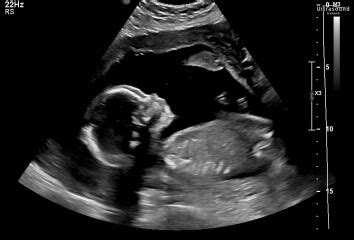

The 20-week scan , also known as the anatomy scan, is a crucial milestone during pregnancy. It’s a detailed ultrasound examination typically performed between 18 and 22 weeks to assess the baby’s physical development and identify any potential abnormalities. Understandably, it’s a nerve-wracking time for expectant parents. Discussions on platforms like Mumsnet reveal that many women experience anxiety leading up to this scan, and a significant concern revolves around the possibility of receiving unexpected or unfavorable news. So, how common is it to receive bad news at the 20-week scan? What kind of issues might be detected, and how are these situations typically handled? Let’s dive into these questions, drawing insights from real experiences shared on Mumsnet, to provide a comprehensive overview for those navigating this important stage of pregnancy.